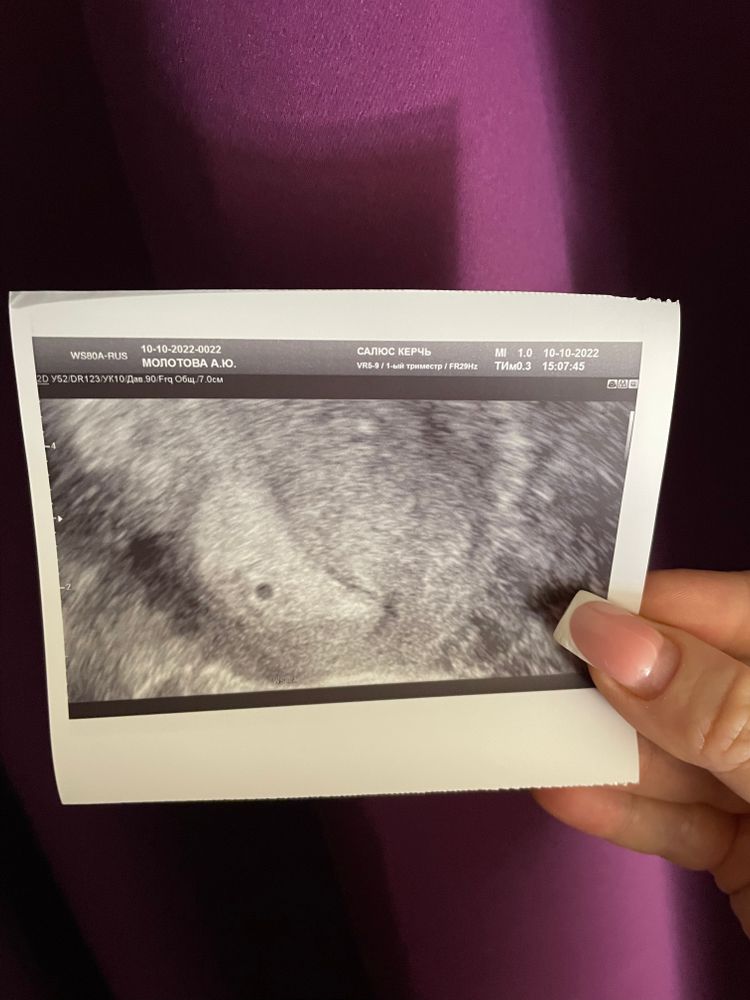

Наше первое УЗИ 🥰

Горошинки быстро растут )))

10.10.2022